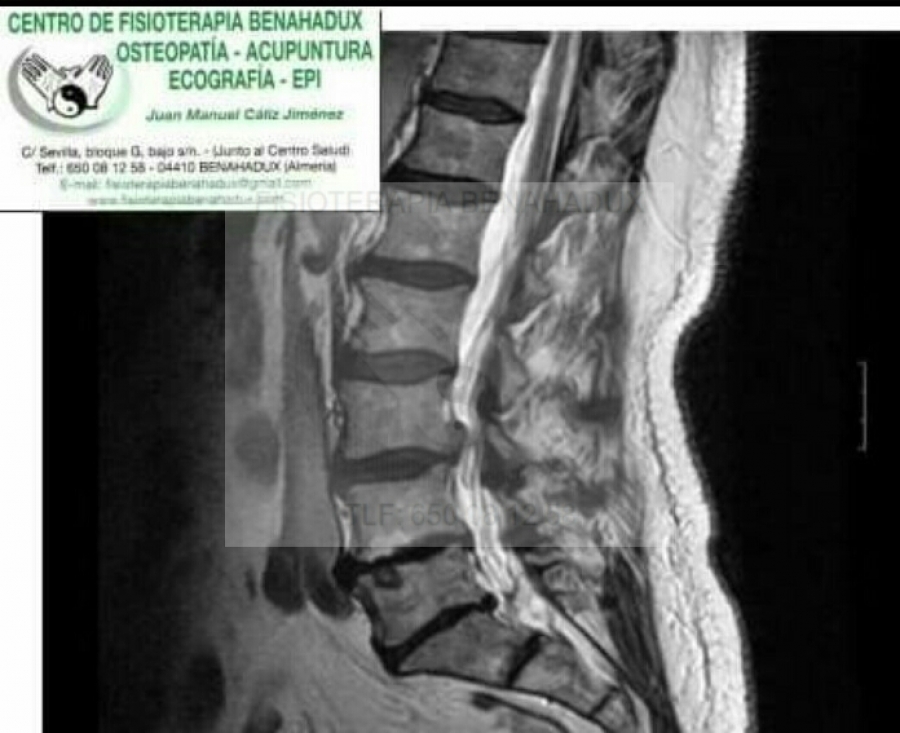

Estenosis foraminal en fisioterapia

ESTENOSIS FORAMINAL

La columna vertebral tiene diferentes funciones la de sostén pero también la de proteger el sistema nervioso. A través de las vértebras pasa la medula espinal y de ahí salen los nervios que van a recorrer todo el cuerpo, dando inervación a las diferentes estructuras. Estos espacios por los que pasa el sistema nervioso tienen que ser de un determinado diámetro para permitir su correcto paso y movilidad . La estenosis de canal es la reducción de estos espacios y por ello pueden llegar a comprimir estas estructuras nerviosas.